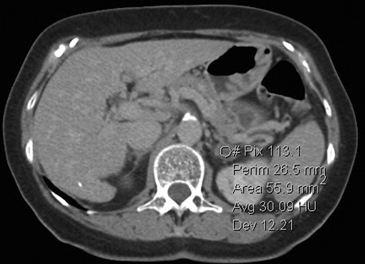

Los valores más utilizados son un 40% de lavado relativo de en fase tardía realizada a los 15 minutos y un lavado absoluto de 60%. De este modo cualquier lesión que muestre un lavado relativo mayor al 40% o absoluto mayor al 60% es consistente con un adenoma, con una sensibilidad y especificidad cercana al 100% (Figura 14 a, b y c). Dado la rapidez con que se obtiene un TAC de abdomen en la actualidad, algunos trabajos han recomendado utilizar cortes tardíos realizados a los 10 minutos, con el fin de optimizar el tiempo de examen, y utilizar un valor relativo de corte más conservador del 50%9.

A

B

C Figura 14. Tomografía computada de un adenoma suprarrenal izquierdo típico. Se ha colocado un circulo que representa la región de interés en la lesión de la glándula suprarrenal izquierda, obteniendo una medición promedio (Avg) expresada en unidades Hounsfield (UH). En fase precontraste (a) su densidad es de 0 UH, (flecha), en fase protovenosa (b) alcanza una densidad de 59 UH (cabeza de flecha), y en fase tardía (c) su lavado es de aproximadamente un 50%, llegando a una densidad de 30 UH.